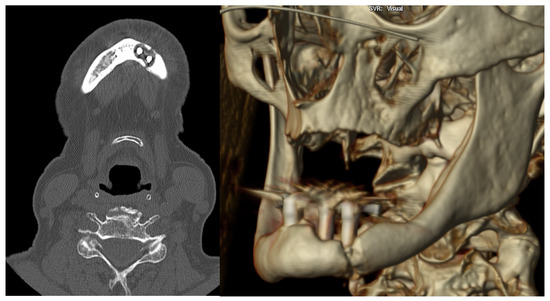

3.1. Case 1

3.2. Case 2

| Diagnostic imaging studies | Orthopantomography (OPG) | 6 (100%) |

| Computed tomography (TC) | 5 (83.3%) | |

| Location | Left parasymphyseal | 2 (33.3%) |

| Left body | 3 (50%) | |

| Bifocal (left body and right ramus) | 1 (16.67%) | |